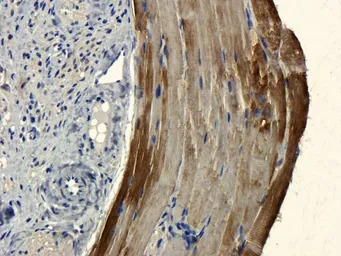

IHC-P analysis of pig small intestine vessel tissue using GTX37364 CD303 antibody.

Dilution : 1:100